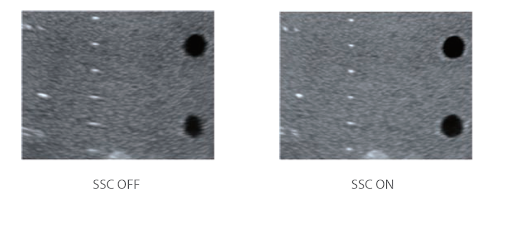

Компенсация скорости звука

С помощью ретроспективного анализа всех полученных данных канала, хранящихся в памяти, система Resona 6 может интеллектуально выбирать оптимальную скорость звука, для улучшения точности отображения каждого вида ткани, обеспечивая таким образом регулируемую тканеспецифическую оптимизацию.